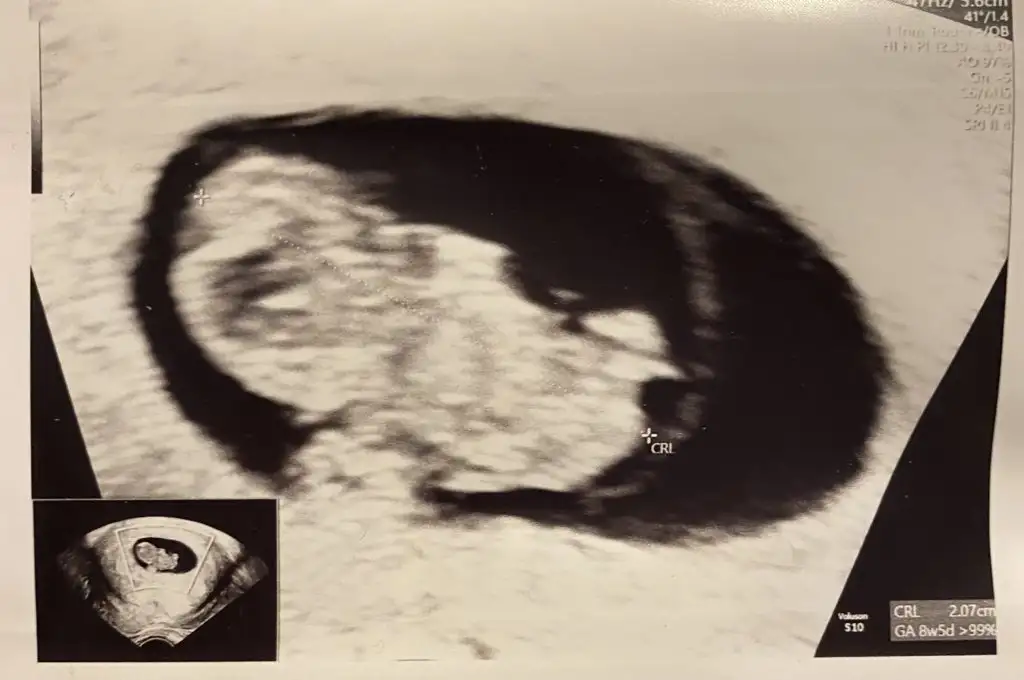

Merhabalar, bana da bakabilir misiniz rica etsem? 8 haftalık vajinadan bakıldı.

Merhaba bana da bakabilir misiniz 6+2 karından ultrason 🥰